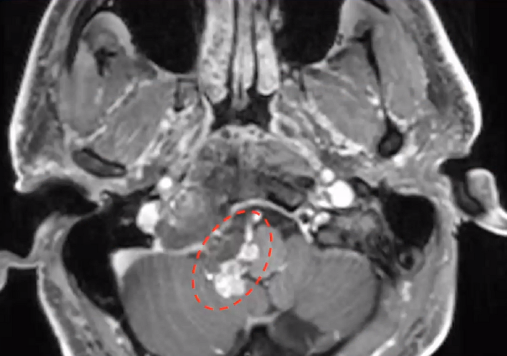

▼这是几年前做的一个手术,先把鼻中隔先推开,然后推开那些正常的组织,这里磨掉枕髁,暴露舌下神经管。虽然很具有挑战性,但是手术做得还是不错的,我们对病人进行了长期的随访,因为我们把全部的就是切开的软组织都复位了,所以看起来还可以,经过内固定以后,病人的颅颈交界区是很稳定的。

▼这个病例,它影响了颈1颈2,然后没有侵袭到硬膜内,我就不考虑用内镜了。考虑到脑脊液的释放等问题,这里我用了后外侧的一个入路。利用45度的内镜往上看,往上磨除岩骨的后方,可以一直暴露颈内动脉的岩骨段,然后海绵窦段。然后在显微镜下我们可以进行双手的操作,神经外科医生就比较熟悉的了。我们在做手术切除肿瘤切完了之后,还要进行固定。

▼这是一个较大肿瘤的案例,它严重影响到枕髁,我们用神经内镜,通过抽吸可以切除大部分,然后和显微镜配合。